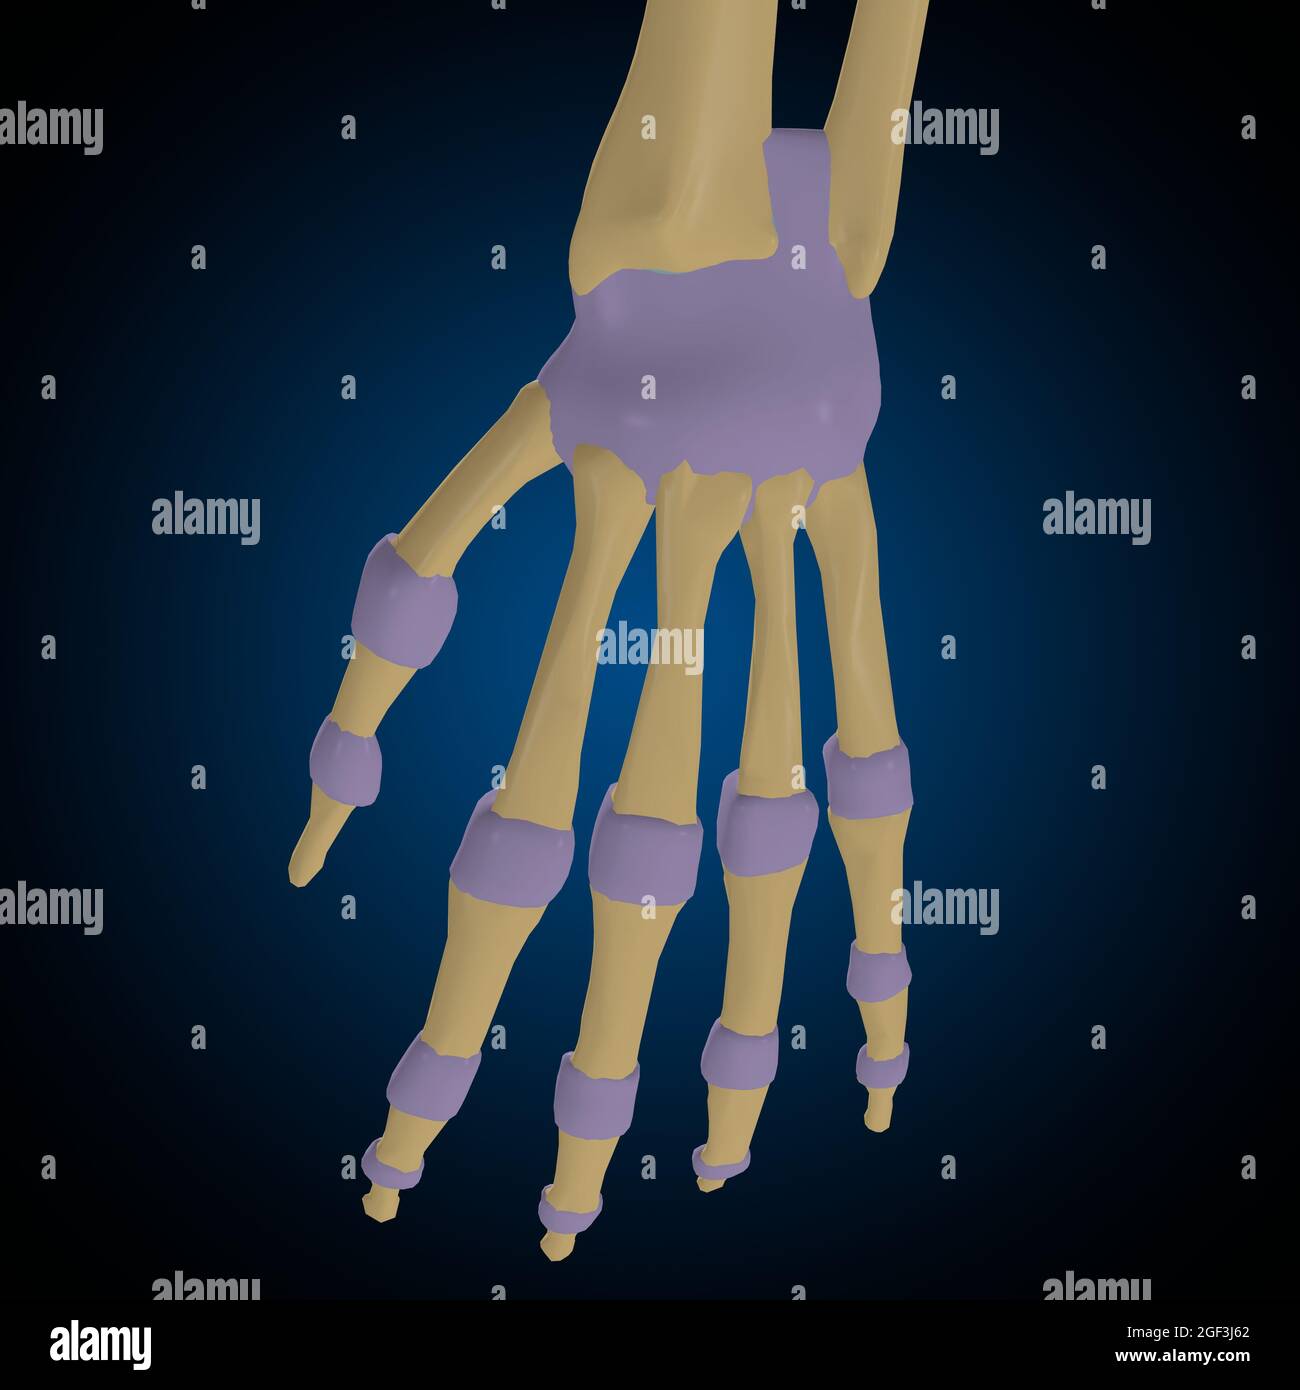

3d rendering of metacarpal Stock Photohttps://www.alamy.com/image-license-details/?v=1https://www.alamy.com/3d-rendering-of-metacarpal-image212538596.html

3d rendering of metacarpal Stock Photohttps://www.alamy.com/image-license-details/?v=1https://www.alamy.com/3d-rendering-of-metacarpal-image212538596.htmlRFP9NY44–3d rendering of metacarpal

3d illustration of the synovial joint of the bone of a hand. Schematic and symbolic graphic representation. Stock Photohttps://www.alamy.com/image-license-details/?v=1https://www.alamy.com/3d-illustration-of-the-synovial-joint-of-the-bone-of-a-hand-schematic-and-symbolic-graphic-representation-image336823581.html

3d illustration of the synovial joint of the bone of a hand. Schematic and symbolic graphic representation. Stock Photohttps://www.alamy.com/image-license-details/?v=1https://www.alamy.com/3d-illustration-of-the-synovial-joint-of-the-bone-of-a-hand-schematic-and-symbolic-graphic-representation-image336823581.htmlRF2AFYHWH–3d illustration of the synovial joint of the bone of a hand. Schematic and symbolic graphic representation.

3d rendering illustration of metacarpal Stock Photohttps://www.alamy.com/image-license-details/?v=1https://www.alamy.com/3d-rendering-illustration-of-metacarpal-image212538578.html

3d rendering illustration of metacarpal Stock Photohttps://www.alamy.com/image-license-details/?v=1https://www.alamy.com/3d-rendering-illustration-of-metacarpal-image212538578.htmlRFP9NY3E–3d rendering illustration of metacarpal

3d illustration of the synovial joint of the bone of a hand. Schematic and symbolic graphic representation. Stock Photohttps://www.alamy.com/image-license-details/?v=1https://www.alamy.com/3d-illustration-of-the-synovial-joint-of-the-bone-of-a-hand-schematic-and-symbolic-graphic-representation-image336823590.html

3d illustration of the synovial joint of the bone of a hand. Schematic and symbolic graphic representation. Stock Photohttps://www.alamy.com/image-license-details/?v=1https://www.alamy.com/3d-illustration-of-the-synovial-joint-of-the-bone-of-a-hand-schematic-and-symbolic-graphic-representation-image336823590.htmlRF2AFYHWX–3d illustration of the synovial joint of the bone of a hand. Schematic and symbolic graphic representation.

3d rendering of metacarpal Stock Photohttps://www.alamy.com/image-license-details/?v=1https://www.alamy.com/3d-rendering-of-metacarpal-image212538382.html

3d rendering of metacarpal Stock Photohttps://www.alamy.com/image-license-details/?v=1https://www.alamy.com/3d-rendering-of-metacarpal-image212538382.htmlRFP9NXTE–3d rendering of metacarpal